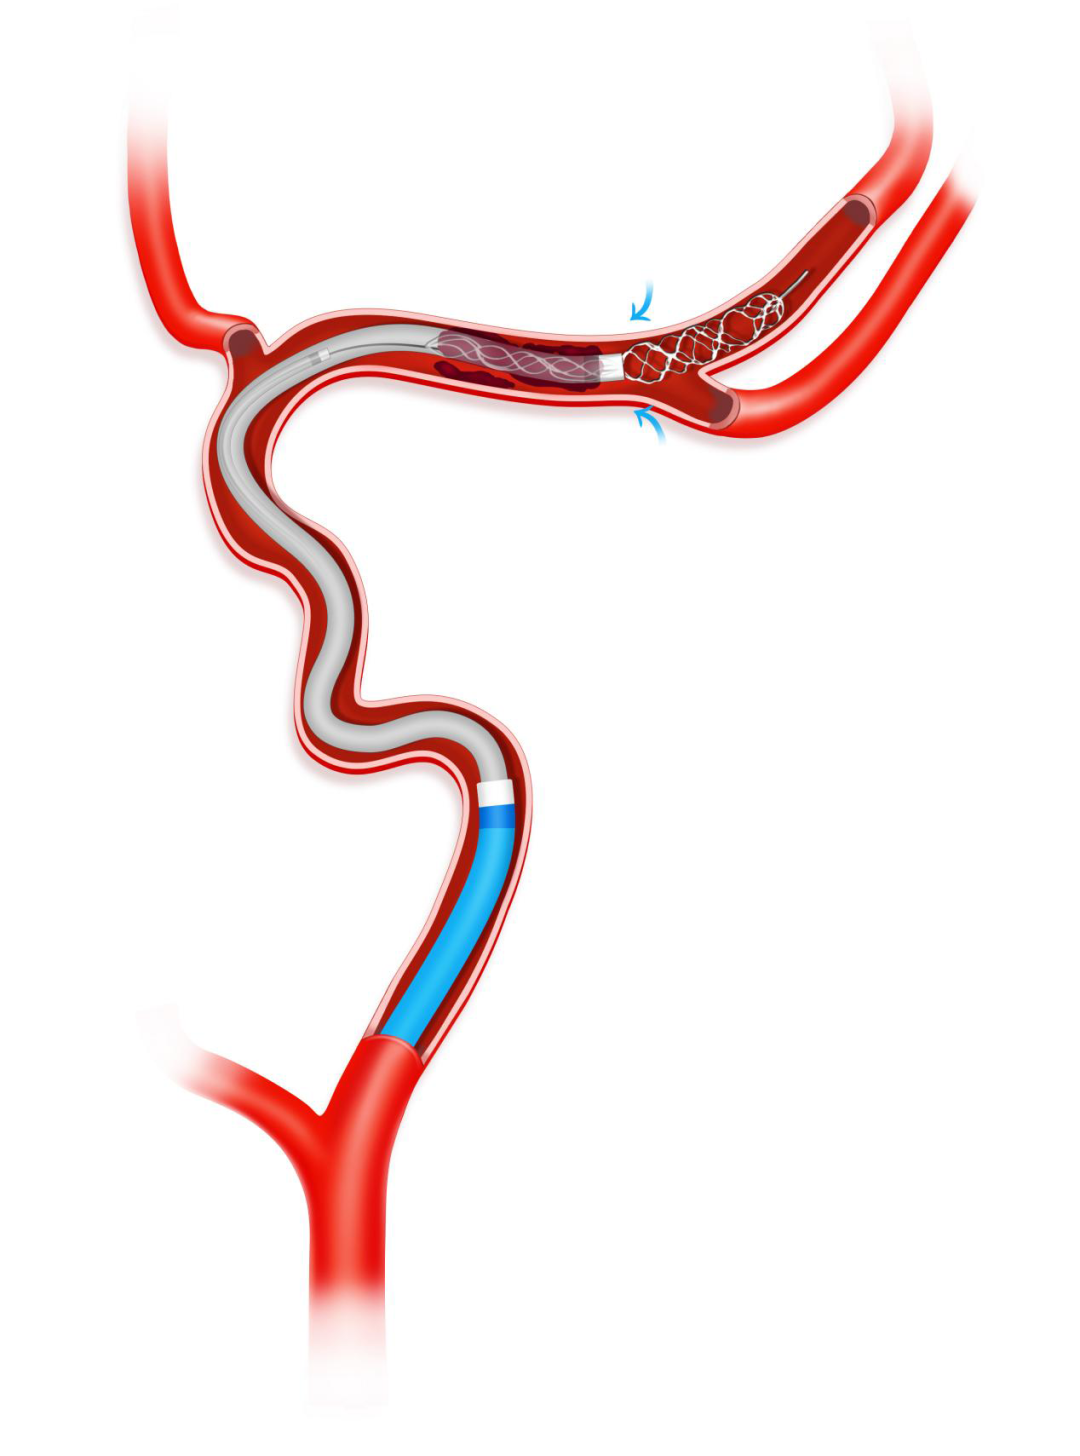

负压下将Syphonet®取栓支架撤回Tethys AS®血栓抽吸导管内。

负压下将Syphonet®取栓支架和Tethys AS®血栓抽吸导管一起撤出,造影确认再通后结束手术。